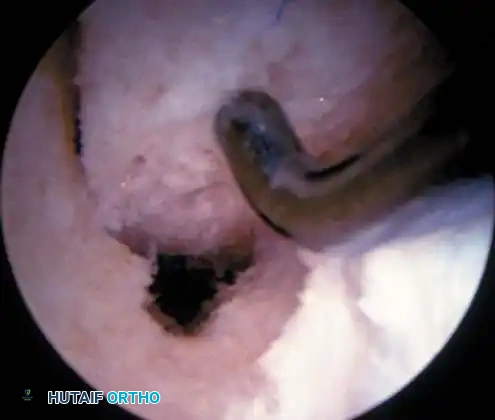

Classifi cation of Meniscal Tears Classifi cation of the types of meniscal tears encountered during diagnostic arthroscopy of the knee is essential in planning the subsequent arthroscopic resection or repair. Although numerous classifi cations of meniscal tears exist, the following, proposed by O’Connor, has proved useful. O’Connor classifi ed the patterns of meniscal tears into the following categories: (1) longitudinal tears; (2) horizontal tears; (3) oblique tears; (4) radial tears (Fig. 48-10); and (5) variations, which include fl ap tears, complex tears, and degenerative meniscal tears. Longitudinal tears most commonly occur as a result of trauma to a reasonably normal meniscus. The tear usually is vertically oriented and may extend completely through the thickness of the meniscus or may extend only partially or incompletely through it. The tear is oriented parallel to the edge of the meniscus, and if the tear is complete, a displaceable inner fragment frequently is produced. When the inner fragment displaces over into the intercondylar notch, it commonly is referred to as a bucket-handle tear (Fig. 48-11). If the tear is near the meniscocapsular attachment of the meniscus, it commonly is referred to as a peripheral

Fig. 48-12 Zone classifi cation of meniscus (modifi ed from Cooper et al.). Most anterior zone of medial meniscus is labeled C, whereas most anterior zone of lateral meniscus is labeled D . 0 is meniscosynovial junction; I is outer third, II is middle third, and III is inner third of each meniscus. (Redrawn from Newman AP, Daniels AU, Burks RT: Principles and decision making in meniscal surgery, Arthroscopy 9:33, 1993.) tear. A peripheral vertical tear in zone I, referred to as a red-red tear, and a tear between zone I and II, referred to as a red-white tear, are in the vascularized portion of the meniscus (Fig. 48-12). These peripheral tears should be repaired when feasible. Horizontal tears tend to be more common in older patients, with the horizontal cleavage plane occurring from shear, which divides the superior and inferior surfaces of the meniscus (see Fig. 48-9B). These are more commonly seen in the posterior half of the medial meniscus or the midsegment of the lateral meniscus. Many fl ap tears and complex tears begin with a horizontal cleavage component.

Oblique tears are full-thickness tears running obliquely from the inner edge of the meniscus out into the body of the meniscus. If the base of the tear is posterior, it is referred to as a posterior oblique tear (see Fig. 48-9C); the base of an anterior oblique tear is in the anterior horn of the meniscus (Fig. 48-13). Radial tears, similar to oblique tears, are vertically oriented, extending from the inner edge of the meniscus toward its periphery, and can be complete or incomplete (see Fig. 48-9D), depending on the extent of involvement. These probably are similar in pathogenesis to oblique tears (Fig. 48-14). The possible variations include fl ap tears, complex tears, and degenerative meniscal tears. Flap tears are similar to oblique tears, but usually have a horizontal cleavage element, rather than being purely vertical in orientation. Tears containing a horizontal element often are referred to as superior or inferior fl ap tears, depending on where the fl ap is based on the surface of the meniscus. Complex tears may contain elements of all of the abovementioned types of tears and are more common in chronic meniscal lesions or in older degenerative menisci. These generally are caused by chronic, long-standing, altered mechanics of the meniscus, and the initial tear occurring in the meniscus may not be identifi able after several different planes of tearing have resulted. Degenerative tears often refer to complex tears. These present with marked irregularity and complex tearing within the meniscus (see Fig. 48-9E and F). These are most often seen in older patients.